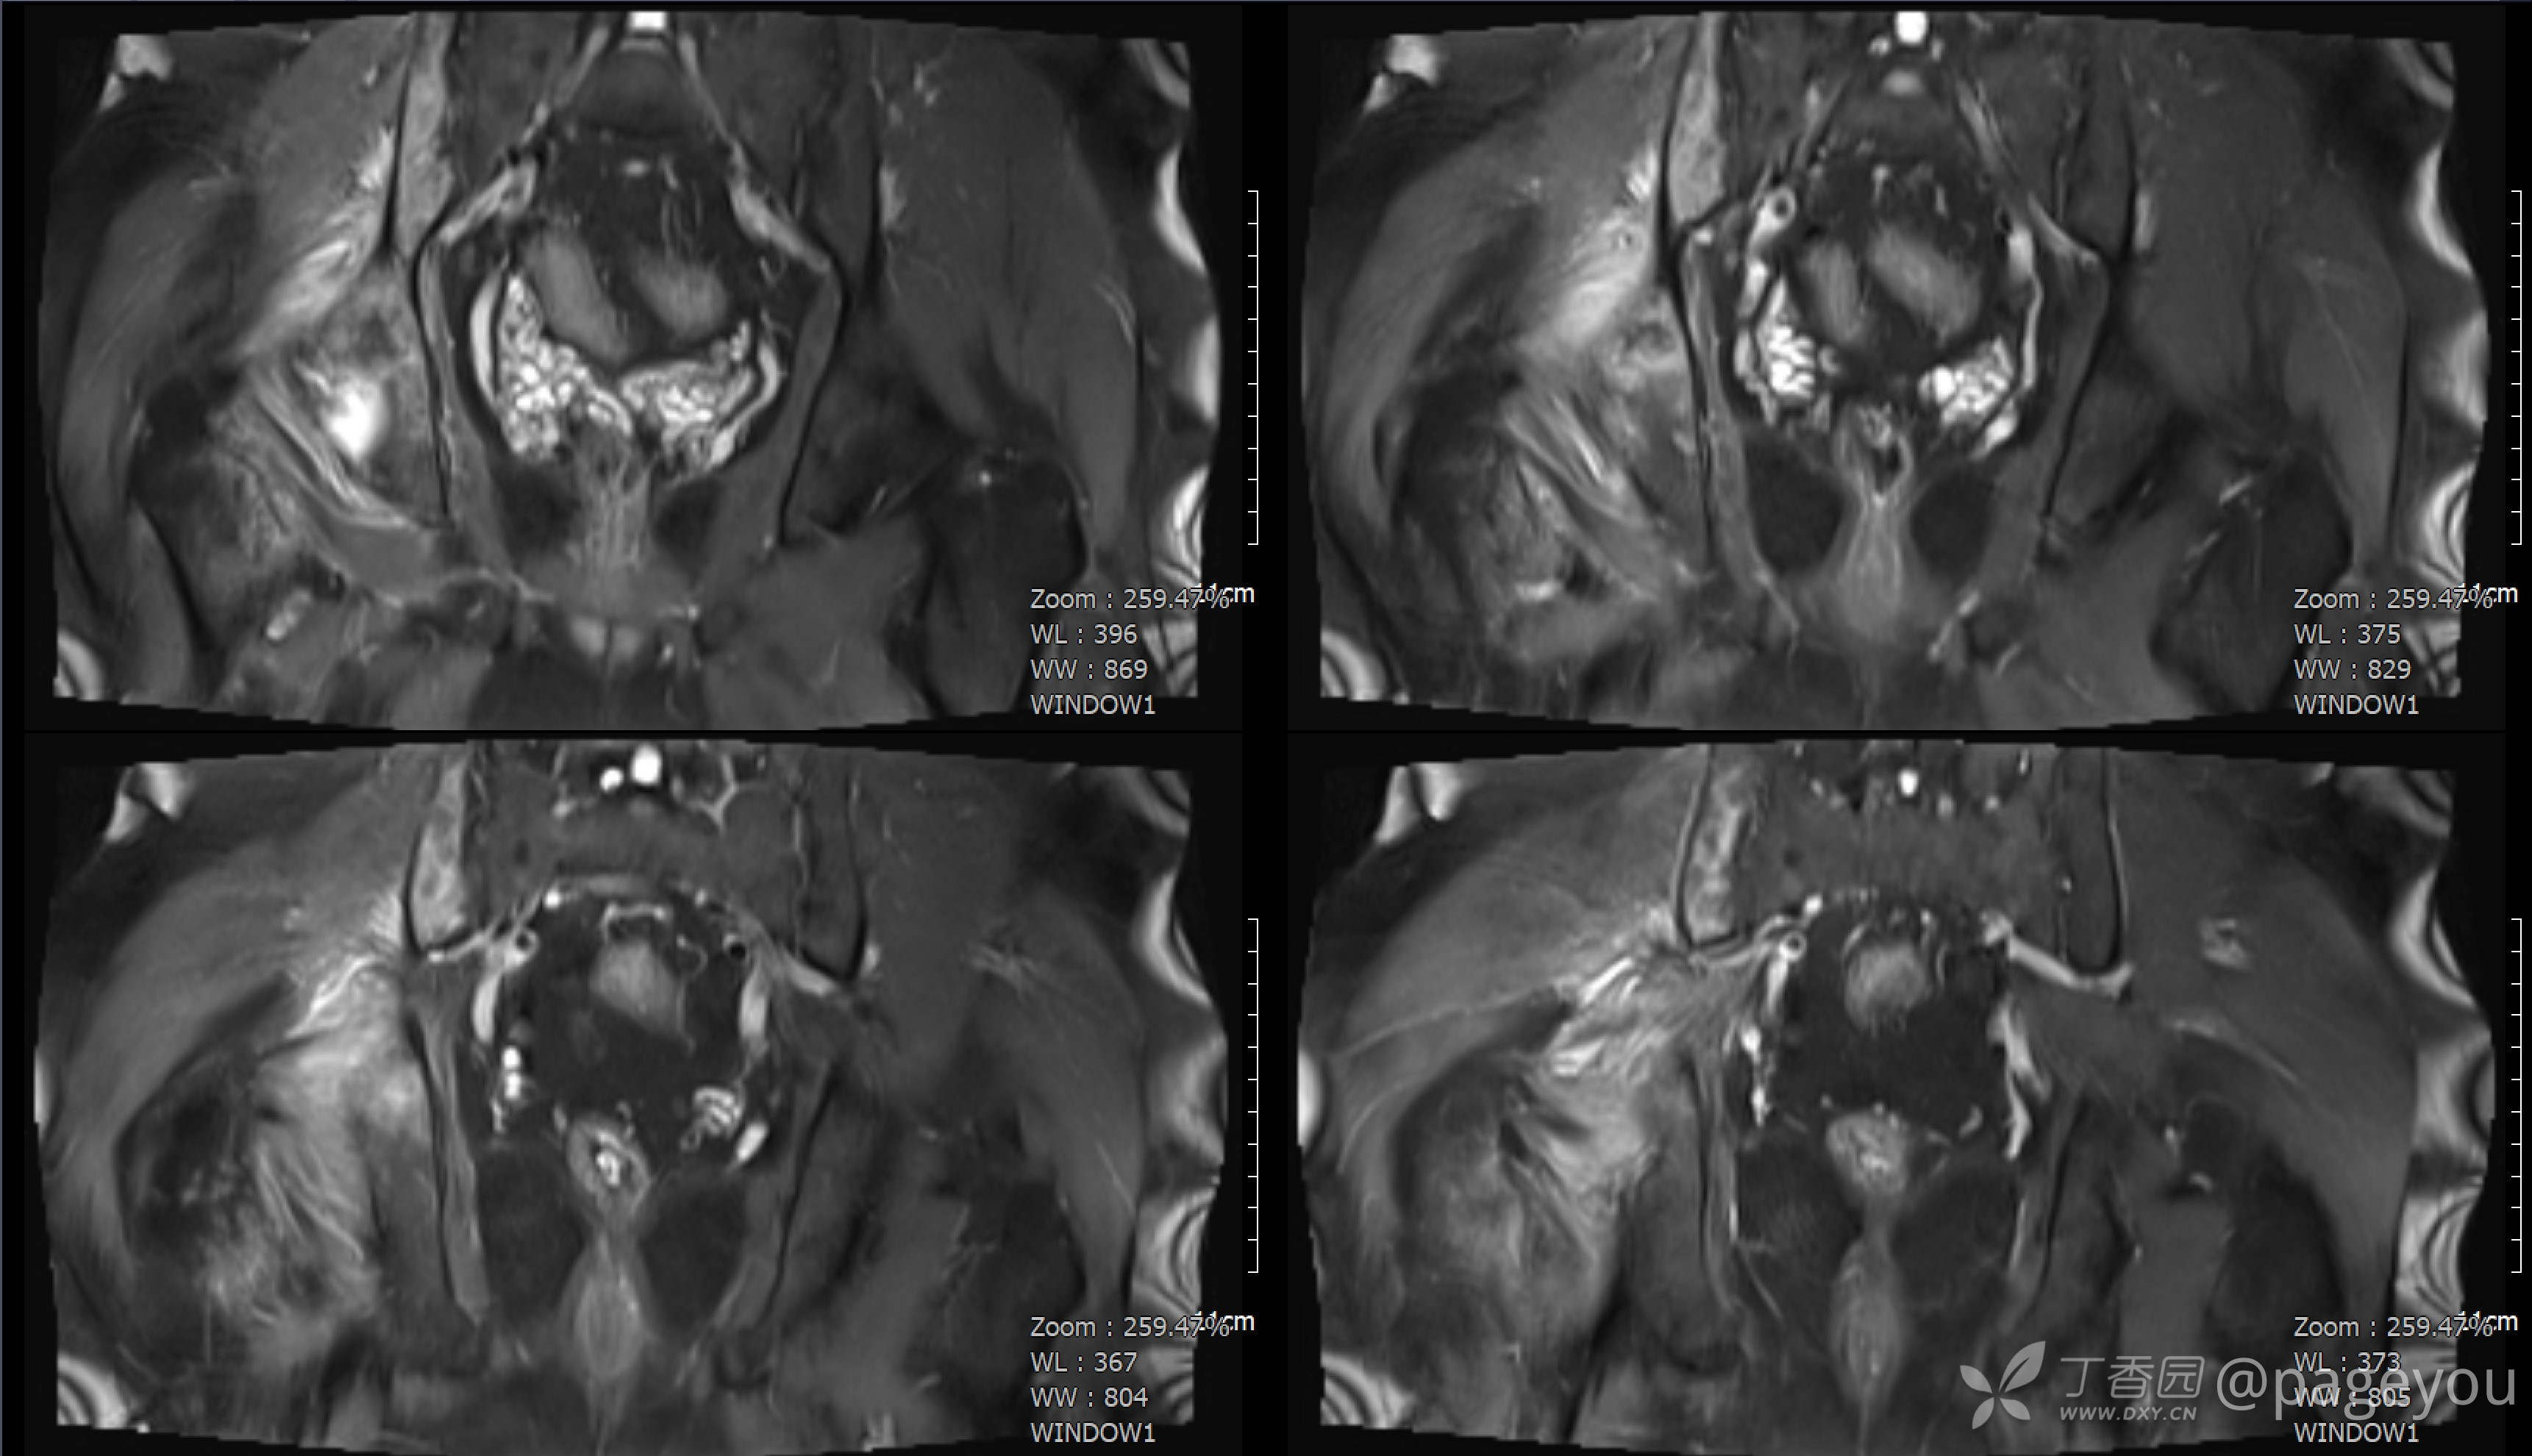

查骨盆MRI: